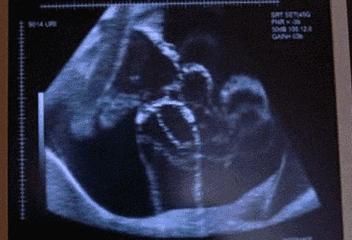

妊娠早期B超检查的主要目的是确定宫内妊娠,排除异位妊娠和滋养细胞疾病,估计孕龄,排除盆腔肿块或子宫异常。

一般在停经35日时,宫腔内可见到妊娠囊;妊娠6周时,可见到胚芽和原始心管搏动。

用B超诊断早孕是最正确可靠的方法。在B型超声波屏上就可显示出子宫内有圆形的光环,又称妊娠环,环内的暗区为羊水,其中还可见有节律的胎心搏动。